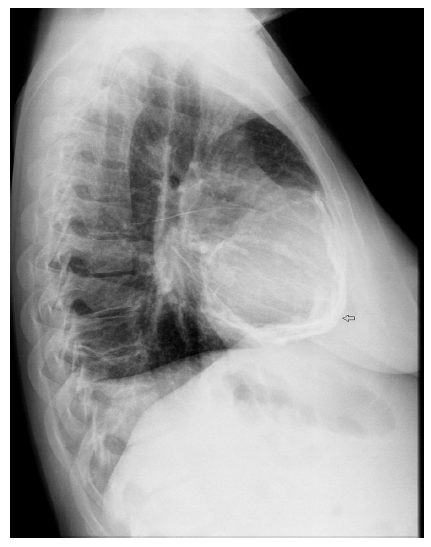

En la radiografía de tórax se evidenció imagen radiopaca alrededor de la silueta cardiaca en patrón de “cáscara de huevo” compatible con calcificación pericárdica difusa y derrame pleural bilateral (fig. 1). El electrocardiograma de 12 derivaciones demostró alteración difusa inespecífica de la repolarización ventricular.